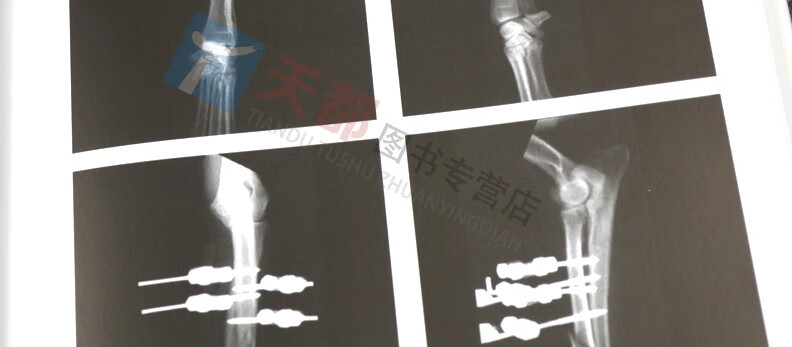

《小動物外固定支架臨床實踐》是小動物臨床中使用線性外固定支架的超實用指導,分為兩部分:第1部分介紹了臨床病例成功實施的基礎知識和科技細節:第二部分篩選了部分病例分析來說明骨折類型及其固定方法。 每一個病例都有治療方法選擇與决定的討論,也附有隨訪X線片來顯示骨折癒合中和癒合後的正常 × 線徵象。